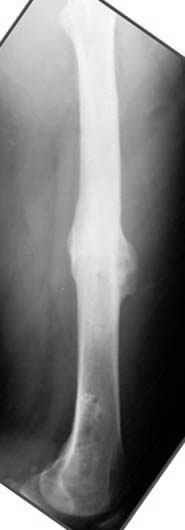

пластическая модель; и коррекция бедра аппаратом Илизарова.

Почему не замена гвоздя с рассверливанием, а аппарат?

Отправитель: Alexander Chelnokov 23 Ноябрь 2004, 21:29

хотя даже если бы и инфекция , то nail exchange с рассверливанием канала - вариант дебрайдмента) Я думаю, что последовательность развития событий:

Узкий к-м канал - тонкий гвоздь- усталостный перелом дистальных винтов - развитие нестабильности и как ее результат остеолиз вокруг гвоздя - деформация анатомической оси бедра. Похоже, что я понял почему аппарат, а не новый гвоздь:-)

Да, наверно. Но если ничего другого нету, ту небольшую деформацию можно было устранить дистрактором одномоментно ввести другой гвоздь.